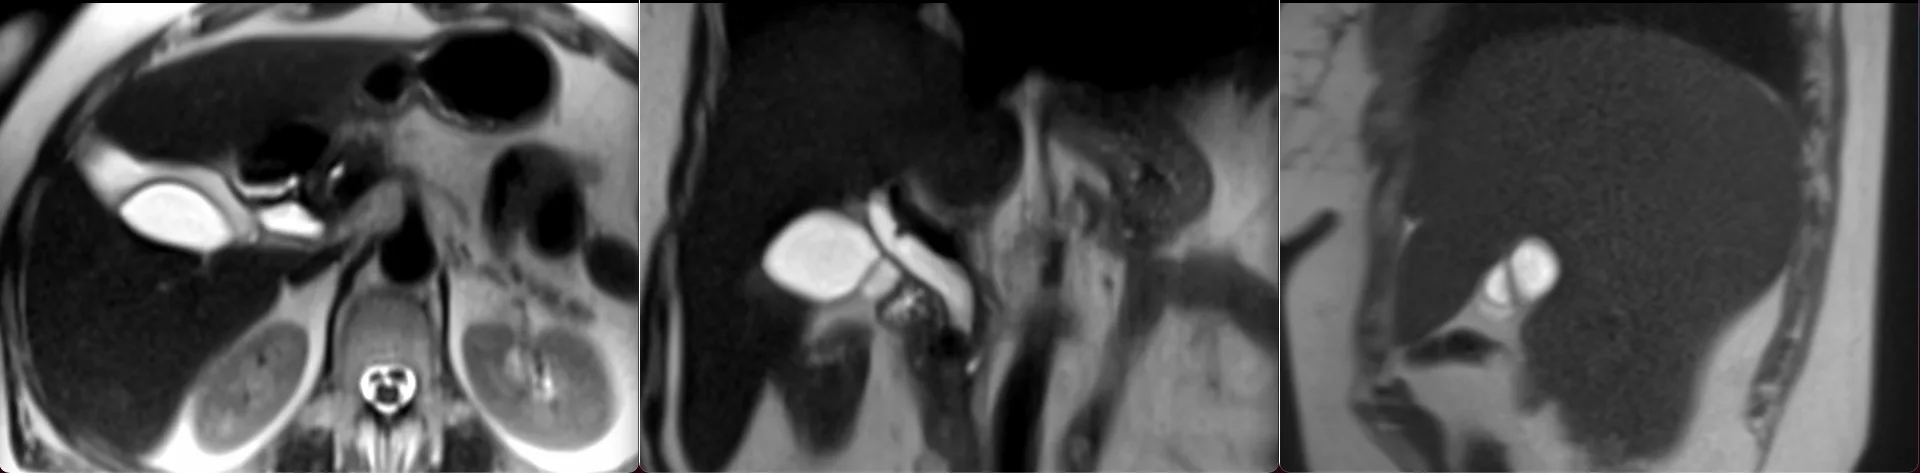

Снеговики бывают разные, но смысл симптома при аденоме гипофиза от этого не меняется: когда опухоль растёт вверх, она протискивается черезу дуральную селлярную диафрагму и в этом месте на ней явственно определяется поясок. Это, как утверждается, достаточно надёжный дифференциально диагностический признак (точность порядка 94-96%) именно аденомы гипофиза, а не какой-то другой опухоли данного расположения.